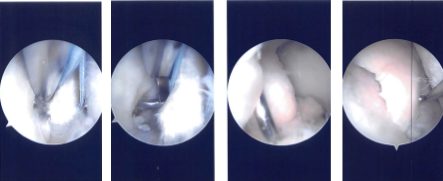

A lateral entry portal was made, and the scope was entered. A tear of the posterior horn of the medial meniscus was found. A medial entry portal was made. The probe was inserted, and the tear was re-examined. It was found to have a root avulsion of the posterior horn of the medial meniscus.

There was patellofemoral arthritis as well as medial femoral condyle arthritis. A decision was made to do the root repair. Chondroplasty of the patellofemoral arthritis which was grade 2 to grade 3 as well as the medial femoral condyle which was grade 3 to grade 4 was performed.

Intraoperative Arthroscopy Images

Curette was used to prepare the bed for the root. FiberWire #2 suture was passed through the root after preparation. Curette was used to prepare the bed by removing the articular cartilage as well as the bone. Scorpion was used to pass the sutures.

ACL zig was used to locate the site for the insertion of the root. Guiding through the ACL zig, an incision was given laterally onto the shin and the guide was inserted. A 2.5-mm drill bit was used to drill to the site of insertion. Finding it satisfactory, a suture retriever was inserted.

The sutures were passed through the suture retriever and retrieved out of the lateral shin of the tibia. Finding it in a satisfactory position on tightening, the sutures were tied over an EndoButton. The knee was irrigated thoroughly.